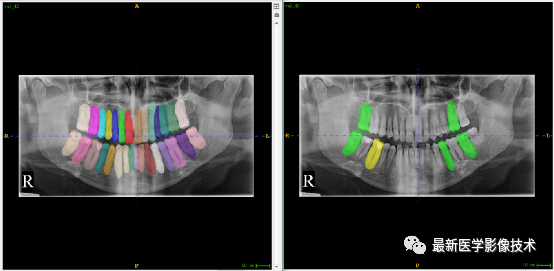

验证集牙齿分割计数和异常牙齿分割识别

左图是分割计数,右图是异常牙齿分割识别结果